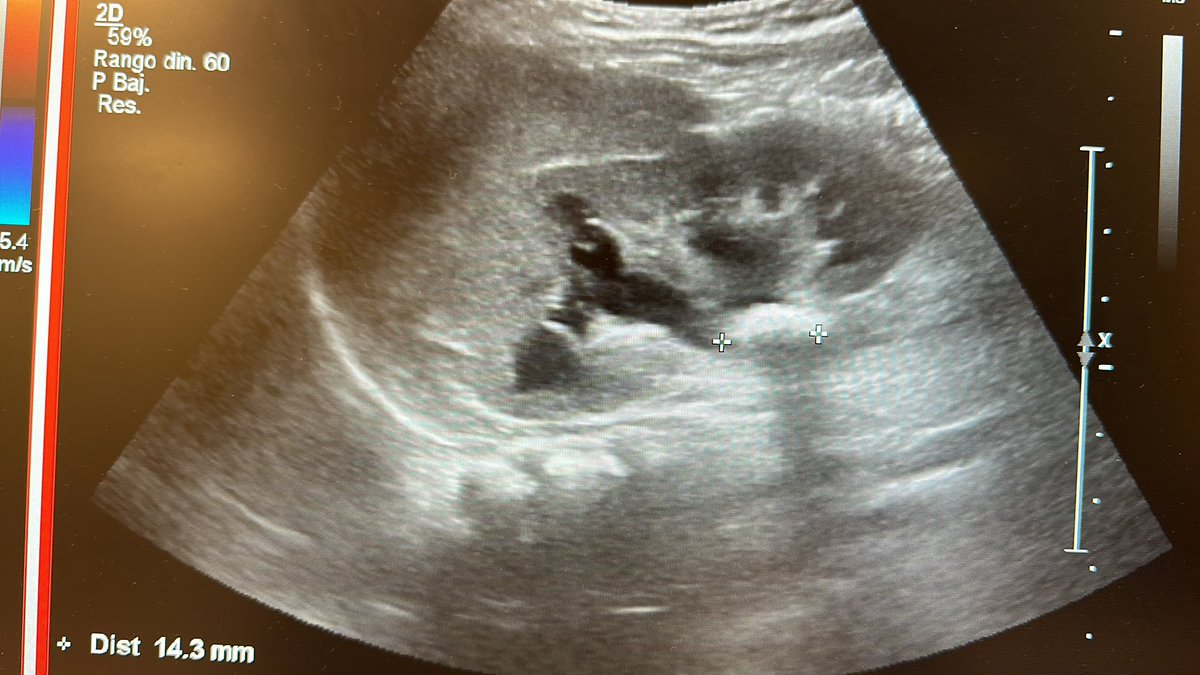

Paciente de 3 años, litiasis renal de 18x14x13 mm y litiasis ureteral.

#lupeyenchile #pedsendourology #endouroinfantil #endourologia #drreed (@pirricu)